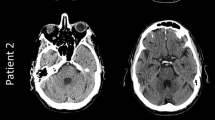

From the first use of the mobCT on November 9, 2021, until March 31, 2021, 61 patients were scanned. Three patients younger than 18 and eight patients who did not undergo an additional stationary CT examination during their hospitalization were excluded. The clinical characteristics of the final study population of 50 patients are shown in Table 2. Figure 1 shows illustrative examples of the findings and of the image quality. The stationary CT scanners included current high-end scanners, with 26 examinations performed on Ingenuity, 10 on Ingenuity Core 128, 6 on Somatom Definition Flash, 6 on IQon Spectral CT, and 2 on Aquilion One. Scanner parameters are shown in Table 1.

Images chosen to illustrate common findings in mobCT images (upper row) and corresponding stationary CT images (lower row). Upper panel from left to right: post craniotomy, subdural hematoma, intracerebral hematoma, and posterior fossa intracerebral hematoma. Lower panel from left to right: brain infarct, subarachnoid hemorrhage and a coiled aneurysm, trauma (motor vehicle accident), and shunt dysfunction with hydrocephalus